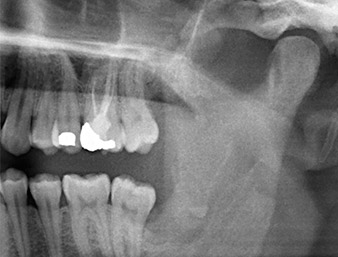

Der Wurzelrest regio 38 zeigte bereits in der Panoramaschichtaufnahme eine enge Lagebeziehung zum Nervus alveolaris inferior. (Abb. 1)

Panoramaschicht-Aufnahme

Abb. 1: Panoramaschicht-Aufnahme 6 Monate nach Osteotomie Zahn 38: Radix relicta liegt nahe dem Nervus alveolaris inferior.

Unser Patient besaß anamnestisch gute Voraussetzungen (Nichtraucher, 26 Jahre) für einen erfolgreichen Eingriff. Wegen des Hinweises auf enge Lagebeziehung des Wurzelrestes zum N. alveolaris inferior in der Panoramaschicht-Aufnahme wurde zusätzlich eine digitale Volumentomografie erstellt (6).